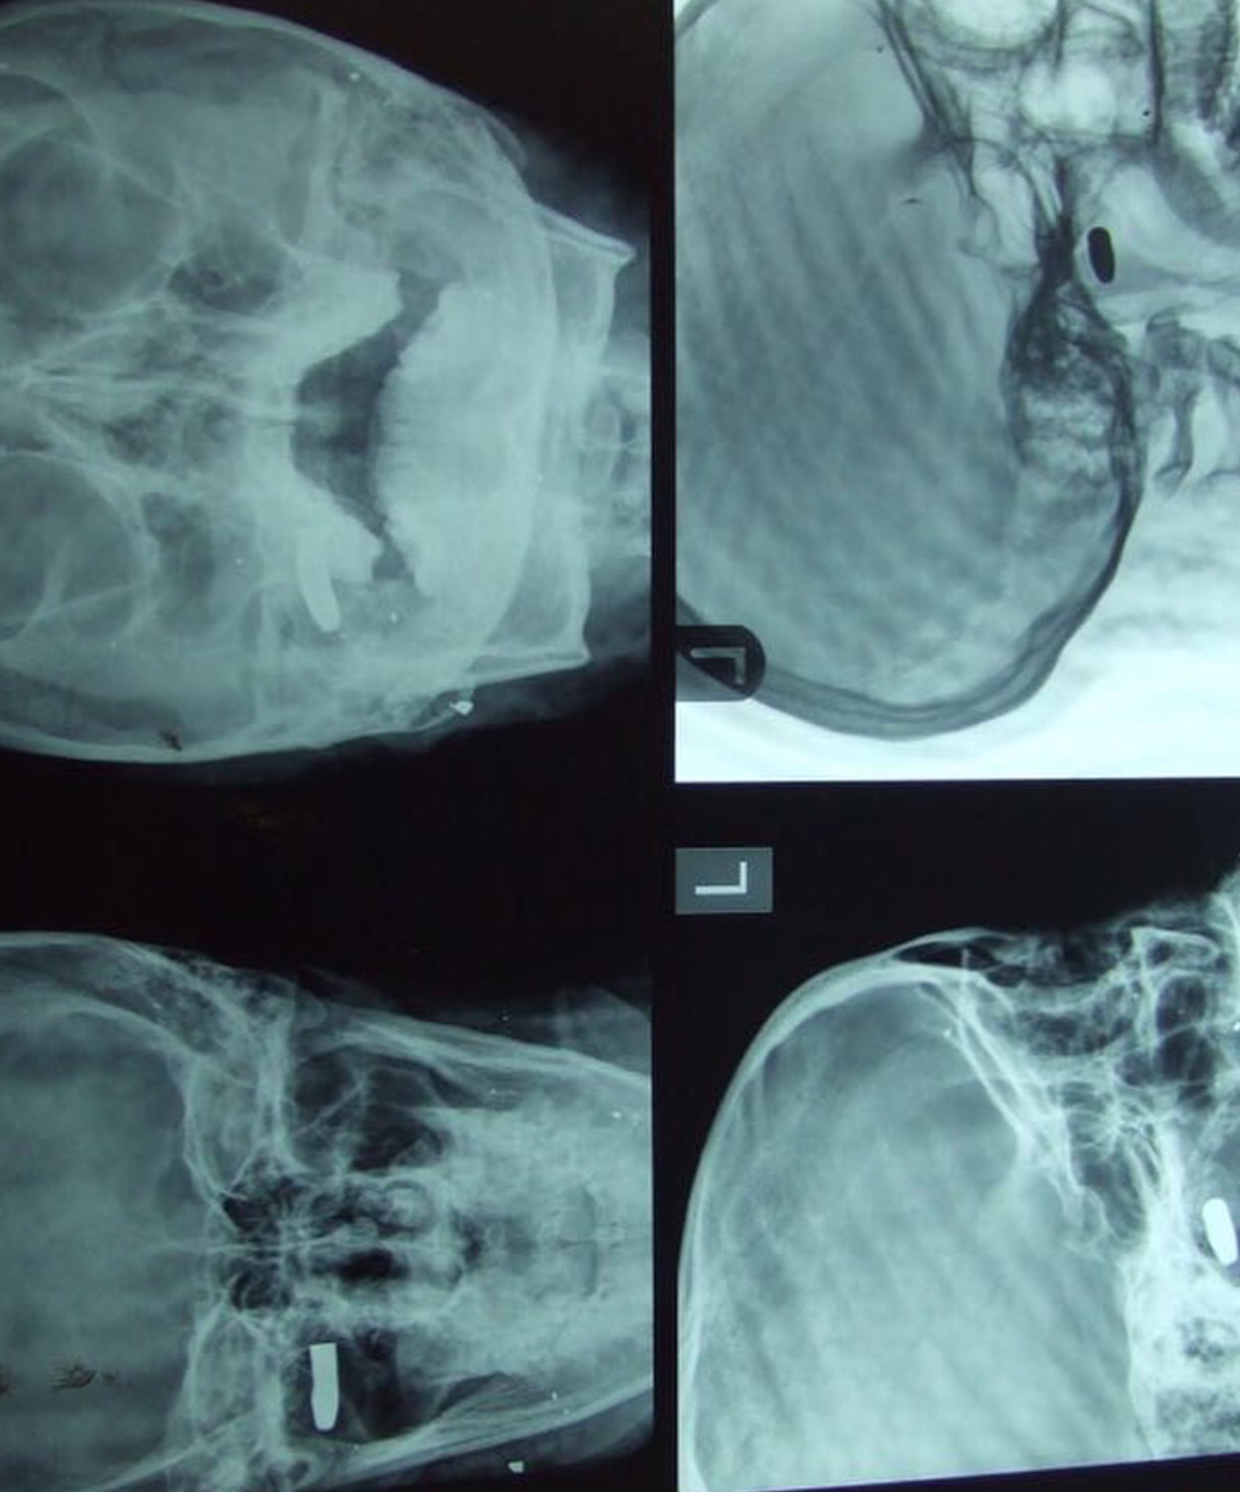

Nigerian artiste and nudist Maheeda celebrates her birthday today. She took to social media to recounts how she was prayed for by a girl, after she was shot by armed robbers. Read what she wrote and the pictures she shared below: